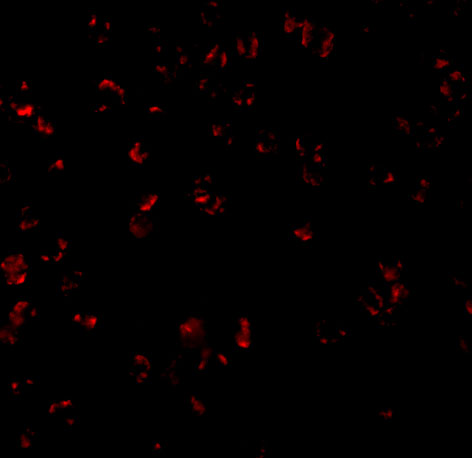

Cytoplasm, perinuclear region. Membrane raft. Appears to have a perinuclear, compact and filamentous pattern of expression. Also found in the nucleus of several types of tumor cells. Colocalized with DPP4 in membrane rafts.